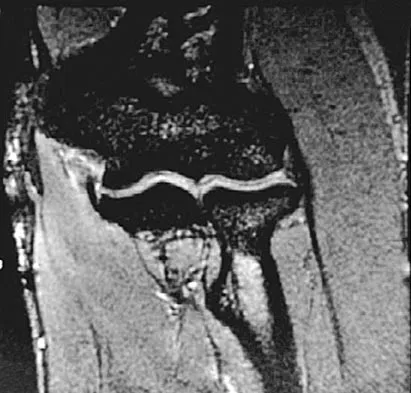

A 26-year-old man has recurrent right knee pain. Figures 9a and 9b show consecutive sagittal T2-weighted MRI scans, and Figure 9c shows a coronal T1-weighted MRI scan. What is the most likely diagnosis?

A 14-year-old girl reports bilateral patellofemoral symptoms. Based on the radiograph and MRI scans shown in Figures 23a through 23d, what is the next most appropriate step in management of the lesion?